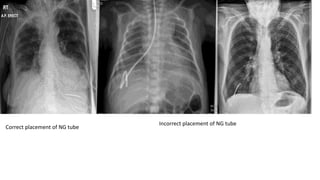

Nasogastric and nasoenteric Tubes.

• Tubes passes through the nose and down into the stomach or small

intestine.

• Has several purpose as feeding , decompression , radiographic

examination.

• Levine and Salem-sump tubes are often sued.

• Don’t disturb the tube while taking radiograph .

• If it has to be disconnected from suction ,temporarily take permission

from the nurse.

• While giving oral contrast through tube make sure not to displace

tube from its location .

Correct placement of NG tube

Incorrect placement of NG tube

Correct placement ofNG tube Incorrect placement of NG tube